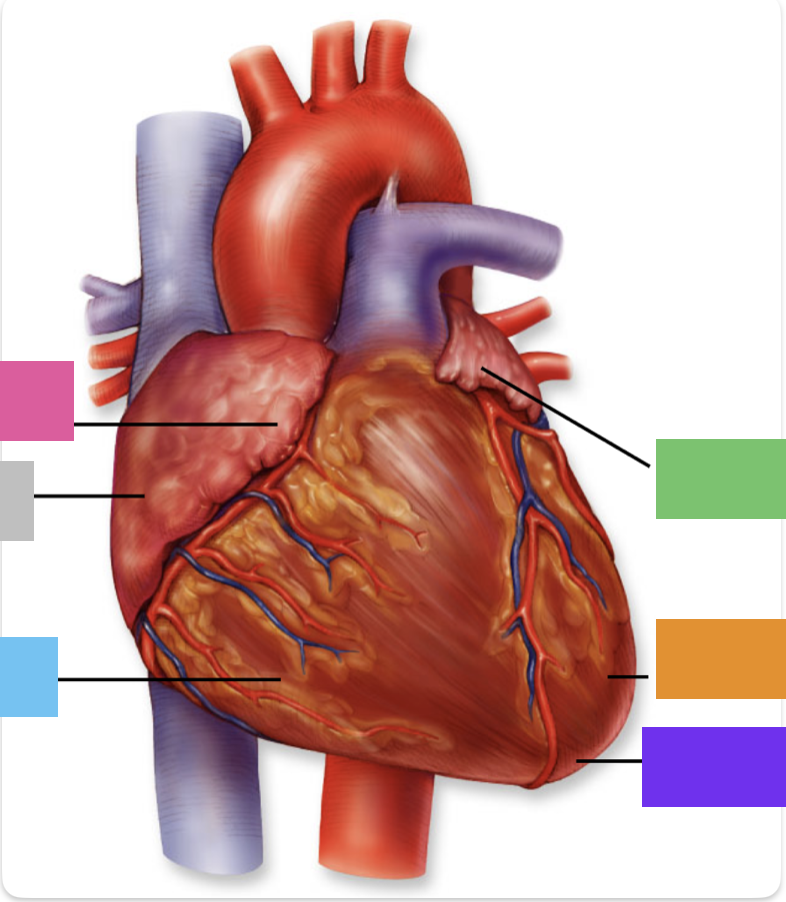

light purple

base

purple

apex

grey

right atrium

pink

right auricle

green

left atrium

green

left auricle

blue

right ventricle

orange

left ventricle

green

coronary (atrioventricular) sulcus

pink

interatrial septum

dark blue

interventricular septum

green

anterior interventricular sulcus

green

posterior interventricular sulcus

right coronary artery

posterior interventricular artery

left coronary artery

anterior interventricular artery

circumflex artery